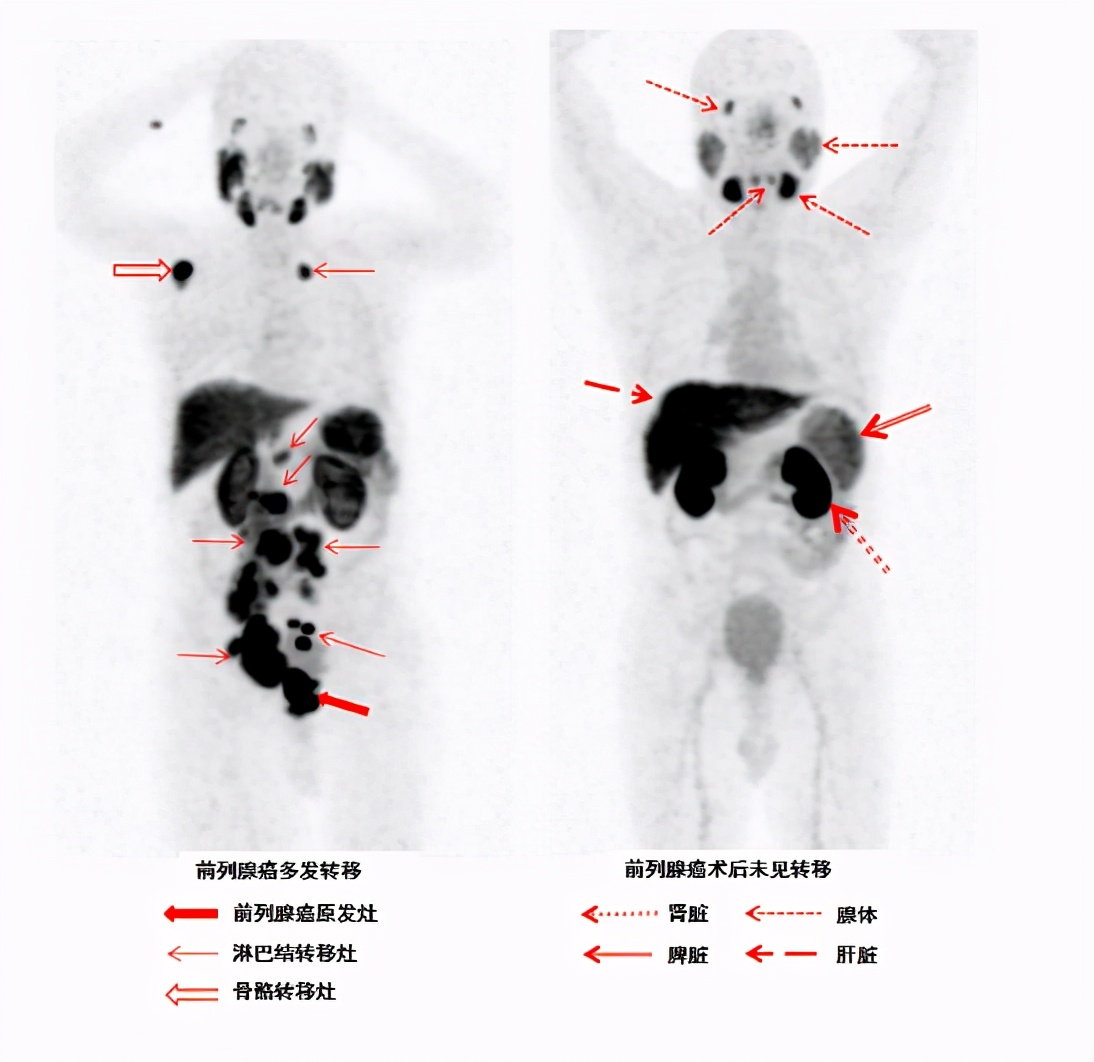

18F-PSMA-1007 PET/CT是一种基于PSMA的分子成像技术。PSMA-1007是一种PSMA*制剂抑**,可以特异性的与前列腺癌细胞结合,当我们连接核素后称为18F-PSMA-1007,当它经静脉注射后可迅速、准确地定位PSMA高表达的前列腺癌病灶和转移病灶,清晰显示原位小病灶,骨骼、淋巴结及内脏器官转移情况,对患者进行无创性的定位、定性、定期诊断。

综上所述,基于18F-PSMA-1007的PET/CT显像对前列腺癌的高灵敏度和特异性,大大提高了中到高风险的原发性前列腺癌在淋巴结、骨以及其他器官的转移检出率,避免患者进行不必要的检查同时改良治疗方案。此外,18F-PSMA-1007与传统显像手段以及其他示踪剂相比,在PSA升高考虑为复发患者的病灶检出方面更为优秀,为临床医师提供最全面最精准的临床分期,对前列腺癌治疗方案的选择具有重要指导意义。